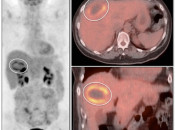

Radiofrequency Ablation of Liver Lesions

Although there is considerable variation in the recommended timing of PET/CT imaging after radiofrequency ablation of liver lesions, PET/CT has shown considerable utility for detecting recurrent/residual disease.

Some advocate post-procedure PET/CT imaging 24-48 hours after ablation to assure that the entire lesion has been fully treated (any remaining FDG uptake at this very early stage should represent residual active tumor, not post-procedural inflammation).

Later follow-up can then often performed, as clinically warranted (often at 3 and 6-months).

Benign Findings:

- Complete absence of metabolic activity in an ablated lesion is consistent with successful treatment.

- A homogeneous rim of well-defined peripheral hypermetabolic activity surrounding a non-avid hypodensity is presumed to represent post-ablation inflammatory changes.

The peripheral nature of this uptake is often best appreciated on the coronal images.

Recurrent/Residual Malignancy:

- Any nodular or focal uptake within or abutting the ablated lesion is highly suspicious for malignancy.